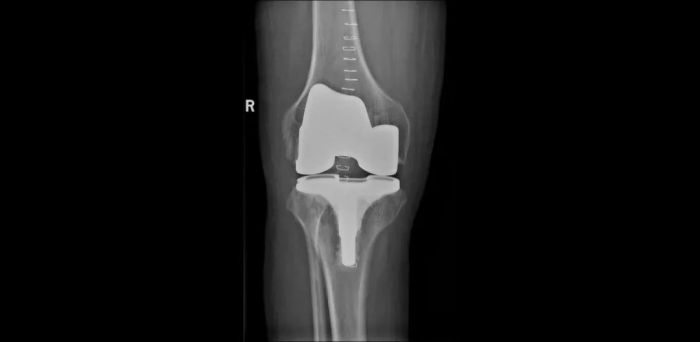

患者术后CT检查结果